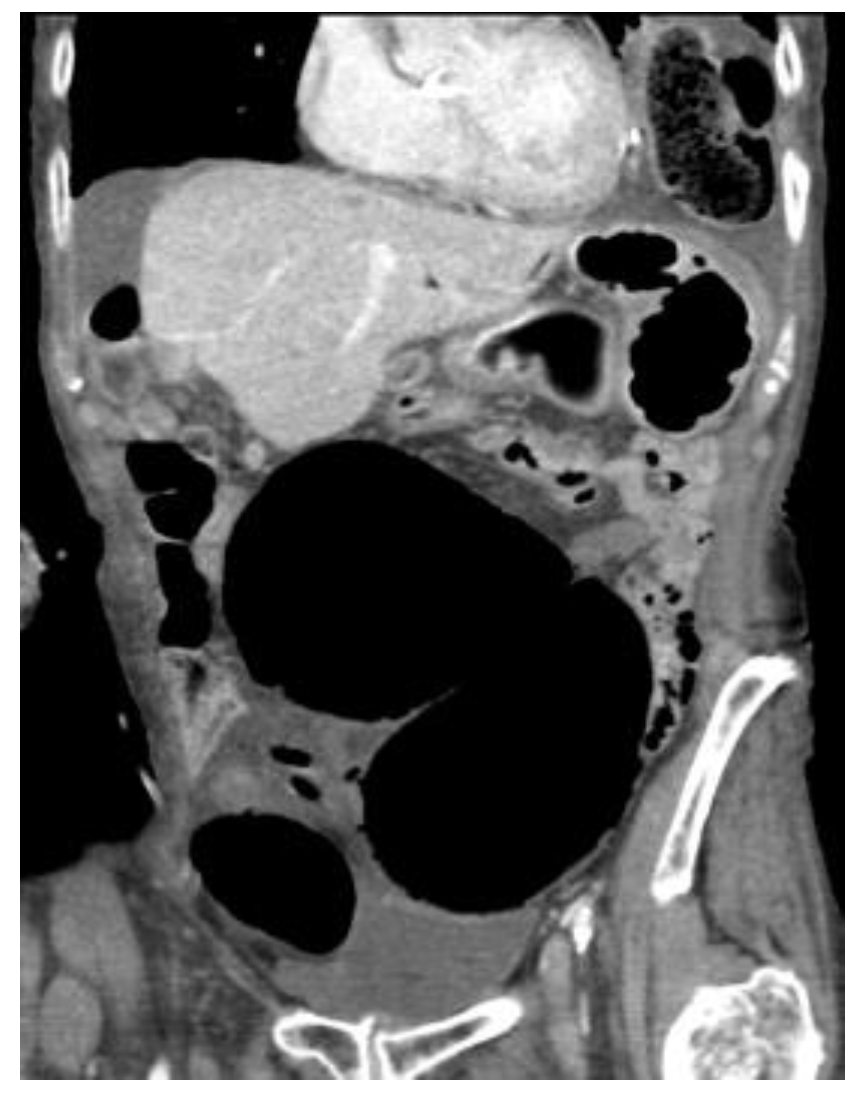

4.4.2. Computerised Tomography (CT) Scan

| CT Abdomen and pelvis | 15 | One patient operated without CT. |

| CV not described | 1 | |

| CV correctly identified | 14 (93.3%) | |

| Caecal diameter >10 cm | 10 (67%) | |

| Whirl sign | 12 (80%) | |

| Split-wall sign | 13 (86.6%) | |

| X-marks-the-spot sign | 14 (93.3%) | |

| Double transition point | 13 (86.6%) | |

| Ileocaecal twist | 13 (86.6%) | |

| Central appendix | 11 (73.3%) |